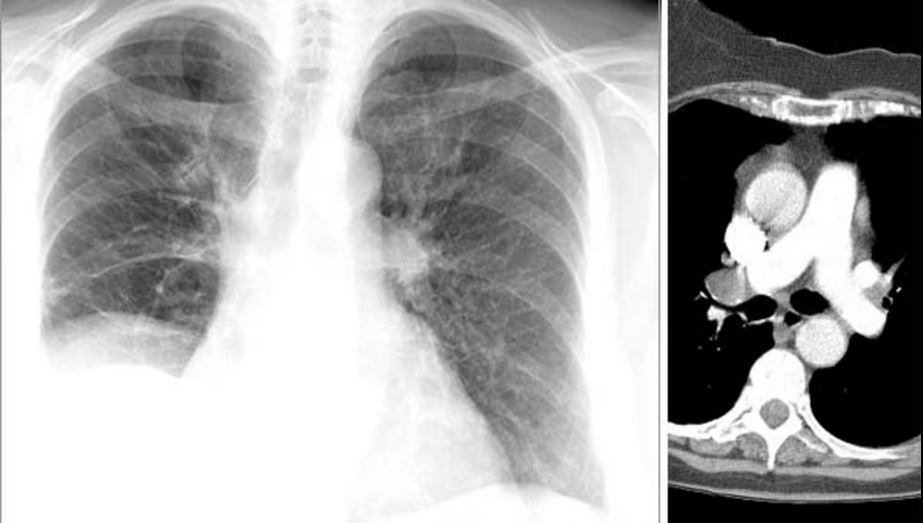

From kingsofradiology.blogspot.com

Bronchial carcinoma Lung Cancer Around Bronchial Tube treatment may include surgery, bronchoscopic treatments that are delivered through a tube with a tiny camera inserted. What are lung carcinoid tumors? — most carcinoid tumors start in the large bronchial tubes leading into the lung. — bronchial carcinoid tumors are carcinoid tumors primarily occurring in relation to a bronchus. Lung cancer usually starts in the airways. Lung Cancer Around Bronchial Tube.

From www.svuhradiology.ie

Lung cancer CXR Radiology at St. Vincent's University Hospital Lung Cancer Around Bronchial Tube Lung carcinoids develop when neuroendocrine cells in. What are lung carcinoid tumors? — bronchial adenoma is a rare type of cancer that starts in the mucous glands and ducts of the lung airways. treatment may include surgery, bronchoscopic treatments that are delivered through a tube with a tiny camera inserted. Your doctor might suggest that you have a. Lung Cancer Around Bronchial Tube.